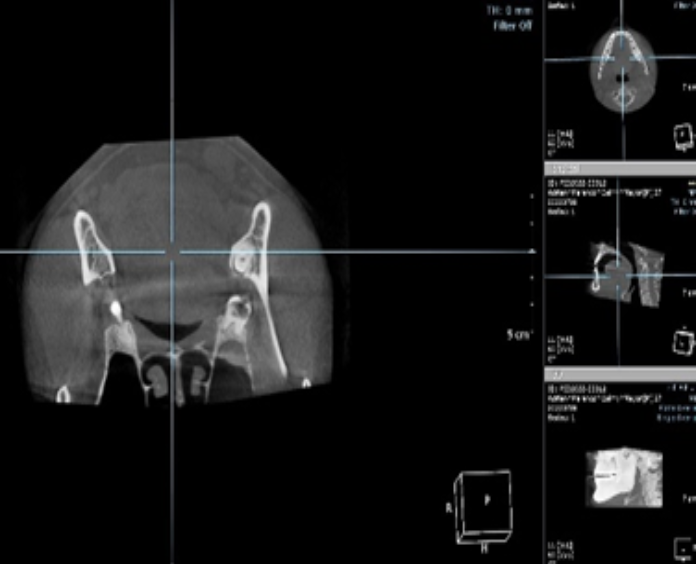

Servicio de

tomografía dental

a todos los dentistas.

Se entregan resultados inmediatos en USB.

Promoción permanente

Tomografía maxilar y mandibular con diagnóstico clínico y radiográfico

por sólo $1500.00 consulta incluida.

Se entrega en USB.

Tomógrafo Dental

Ray Scan